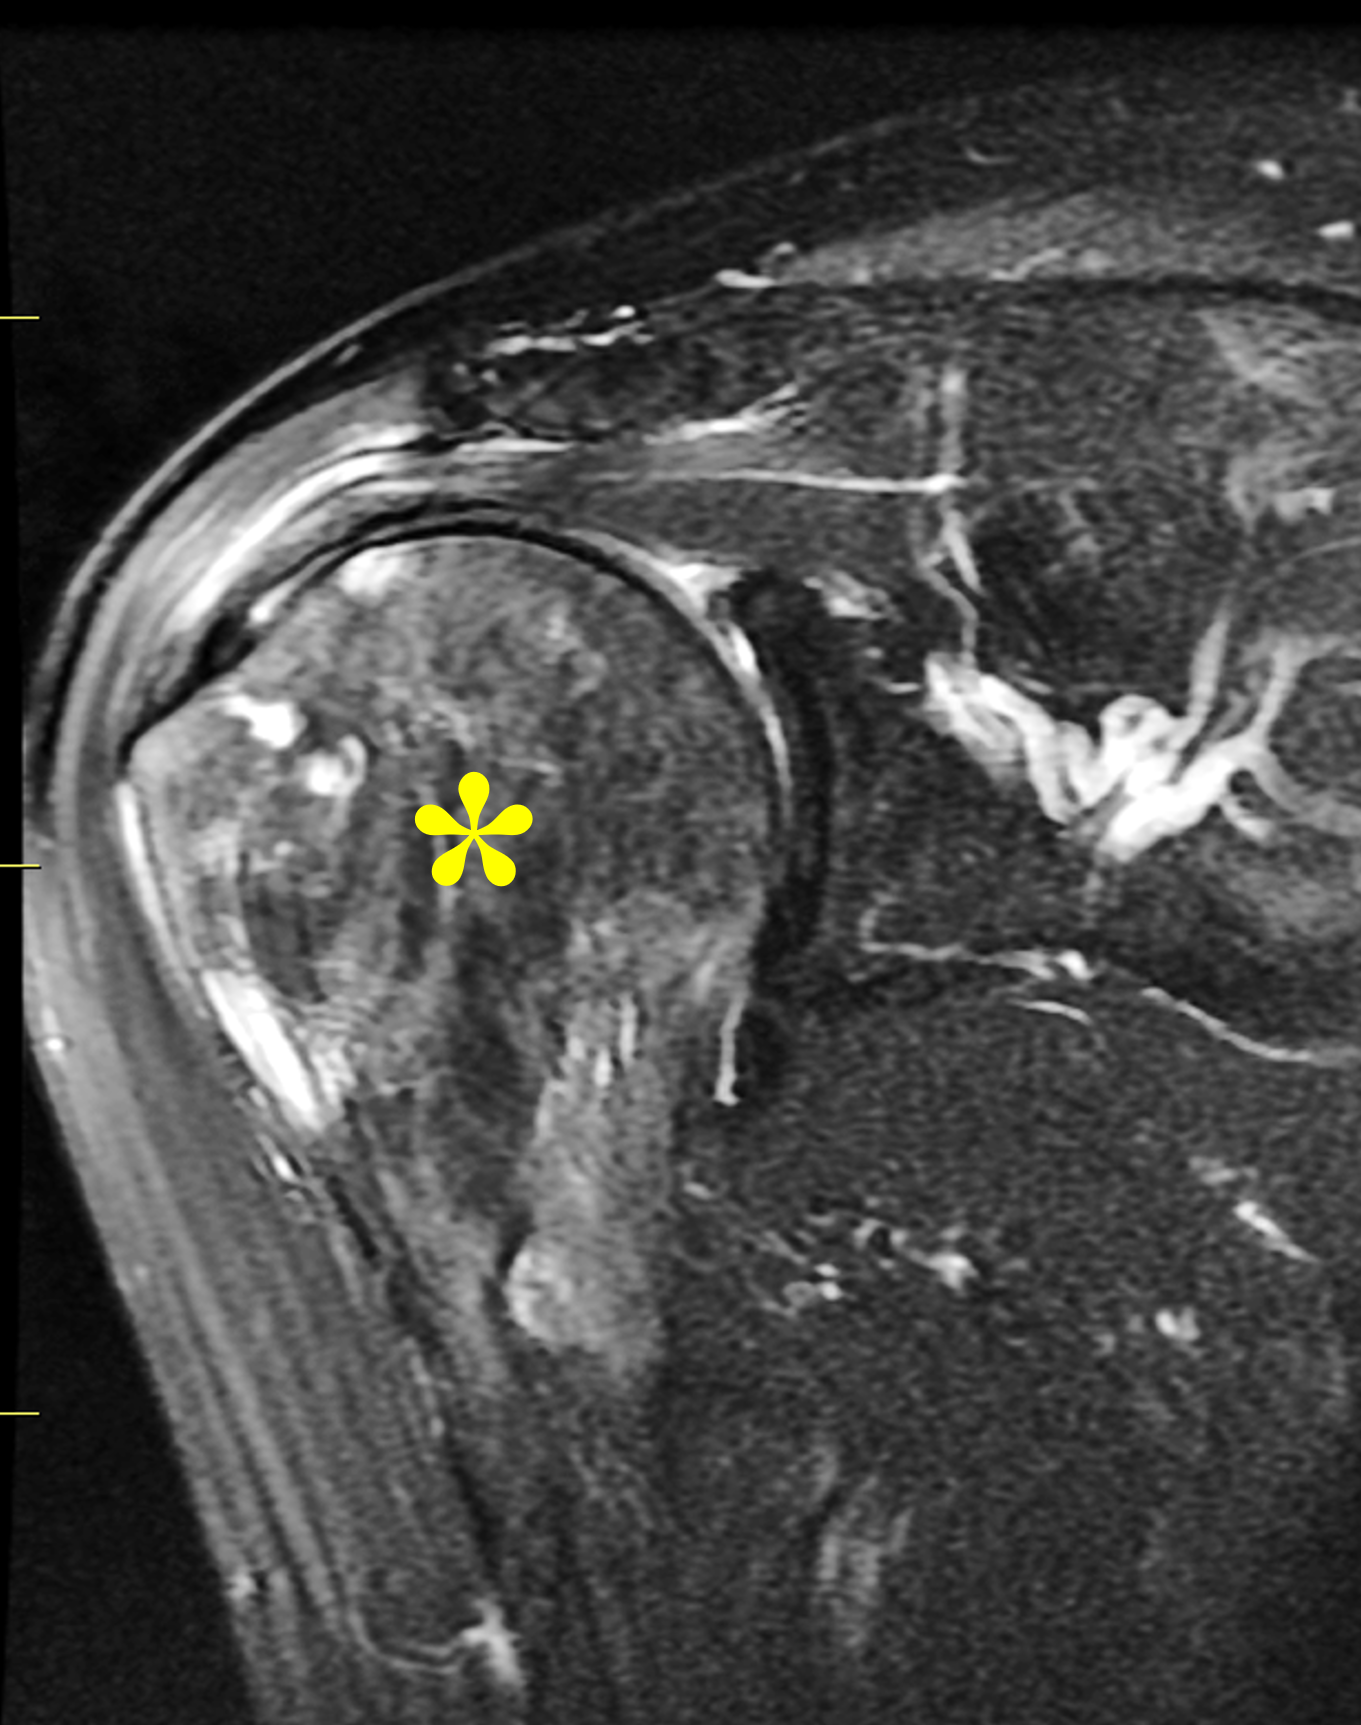

Figure 4: Mixed phase Paget disease of the proximal humerus in a patient with polyostotic disease, MRI pattern 2. (4A) Coronal fat-suppressed, fluid-sensitive image shows heterogeneous marrow (asterisk) with areas of suppressed fat, mildly increased signal, and cystic/tubular high signal intensity areas. (4B) Coronal T1-weighted image shows preserved fat signal (asterisk) within the marrow, as well as thick cortex and trabeculae. (4C) AP radiograph shows typical findings of mixed-phase Paget disease, beginning at the proximal end of the bone and extending distally. Note the sharp demarcation (dotted lines) separating abnormal from normal bone, forming a “flame-shaped” interface. (4D) Bone scintigraphy demonstrates polyostotic disease with intense tracer uptake in the left hemipelvis, sacrum, and a thoracic vertebra in addition to the right proximal humerus.